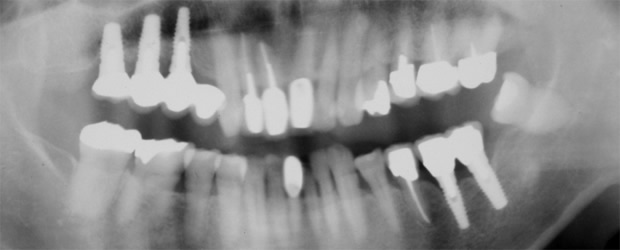

治療後です。左下、右上はインプラント治療を行いました。自分の歯で噛んでいた時のようにしっかりと奥歯で噛むことができるようになりました。天然歯はなるべく削ることなく治療しました。プラークコントロールも上手にされ、歯肉は健康な状態を保っています。

治療後のレントゲン写真です。